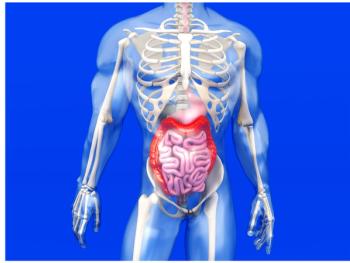

Case History: 62-year-old male with history of abdominal pain and weight loss for two months.

Case History: 62-year-old male with complaint of epigastric pain, retching.